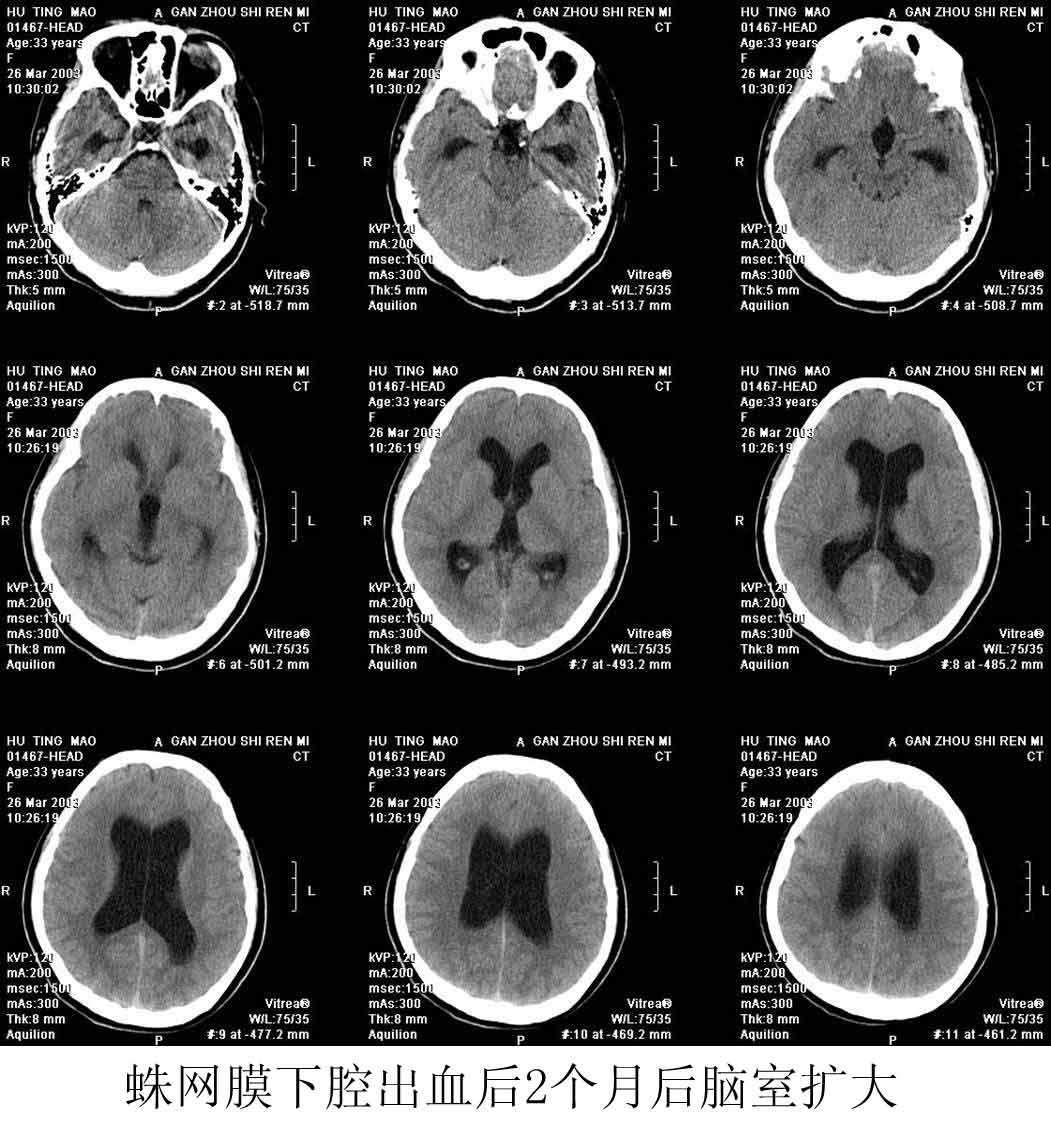

漫谈脑积水的ct诊断

图片尺寸1051x1122

四,有关脑积水的几个问题㈠脑积水的早期ct表现:脑室扩大顺序是侧脑室

图片尺寸640x561